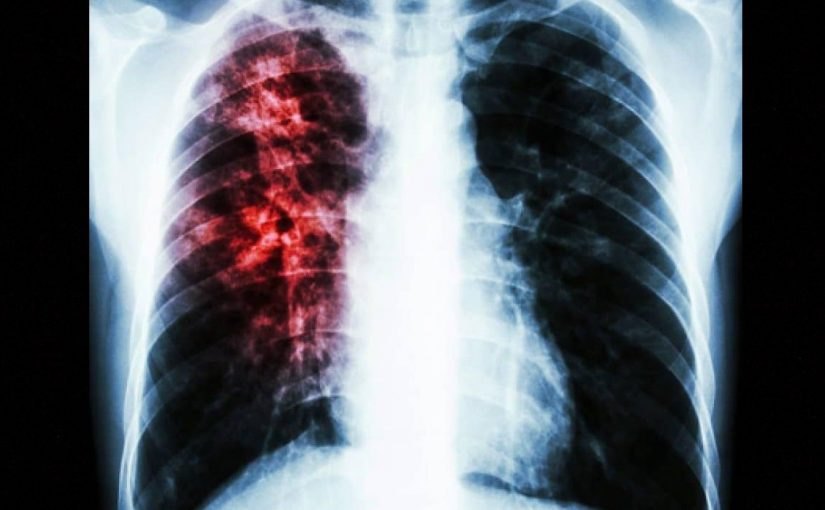

Caused by ‘Mycobacterium tuberculosis’ bacteria that most often affect the lungs, the disease can spread when people sick with TB expel bacteria into the air – for example by coughing.